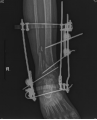

術(shù)后1天復(fù)查X線示:骨折位線良好,關(guān)節(jié)面形態(tài)良好,關(guān)節(jié)間隙正常。外固定架位置適宜。骨折愈合的臨床標(biāo)準(zhǔn):局部無壓痛,無縱向叩擊痛。局部無異?;顒?;X線顯示骨折線模糊,有連續(xù)性骨痂通過骨折線。術(shù)后23周復(fù)查患者骨折模糊,拆除跟骨固定針及脛骨固定半針。術(shù)后25周,骨折處基本達(dá)到臨床愈合標(biāo)準(zhǔn),拆除外固定架,患者可以不住柱拐下地負(fù)重鍛煉(見圖2)。

圖2 患者影像及外觀照片